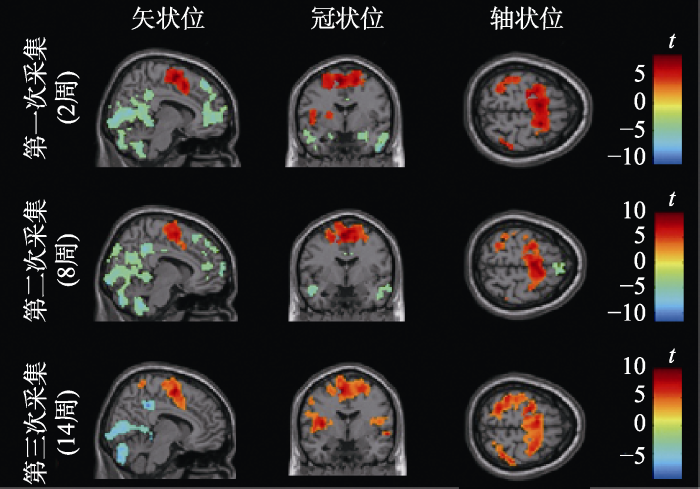

图4

不同时点运动表象激活的脑区

注:校正阈值为体素水平未校正, p < 0.001, 团块水平的FWE校正, p < 0.05; 第一次采集体素数量 > 147, 第二次采集体素数量 > 119, 第三次采集体素数量 > 55。

表3 不同时点运动表象激活的脑区

3.2.2 方差分析

为考察不同时点相关脑区激活的变化情况, 进行单因素重复测量方差分析, 结果显示, 左侧颞上回和左侧楔前叶在不同时点的激活存在显著差异(见表4)。

本研究发现, 运动表象任务在不同时点都激活了类似的额顶认知、运动控制和躯体感觉相关的脑区, 包括额下回、顶下小叶、中央前回、辅助运动区和中央后回等。额顶脑区与高阶认知控制过程相关(Jerde & Curtis, 2013), 中央前回参与运动控制与计划, 辅助运动区还和复杂动作序列的编排有关(Marchand et al., 2013), 而中央后回是参与躯体感觉加工的脑区(Tamè et al., 2016), 三次数据采集都发现了上述脑区的激活, 这可能与太极拳运动表象过程中认知加工和感觉运动加工的整合有关。本研究还发现, 从8周到14周左侧颞上回和左侧楔前叶由表象任务诱发的激活存在显著的增强, 这可能是8周到14周太极拳技能学习过程中, 伴随着技能水平的显著快速提高, 相关脑区激活也显著增强的结果。本研究发现脑区功能的变化和太极拳技能的提高表现出了类似的趋势, 8周到14周既是太极拳技能显著提高的阶段, 也是脑功能显著优化的阶段。而且, 脑和行为的相关分析也发现, 左侧颞上回和左侧楔前叶由表象任务诱发的激活和太极拳的技能水平显著相关, 这进一步说明了太极拳技能学习会对左侧颞上回和左侧楔前叶的功能产生显著的积极影响。值得注意的是, 本研究发现, 从2周到8周, 左侧颞上回的平均信号值虽然出现了暂时的下降, 但是差异并不显著, 推测可能是学习早期, 被试可以利用的已有运动经验较少, 需要不断重复练习单个基本动作, 导致技能的学习出现了一些反复, 表现为这一阶段技能水平变化不大, 因此, 相应的运动表象任务诱发的左侧颞上回的激活也变化不大。